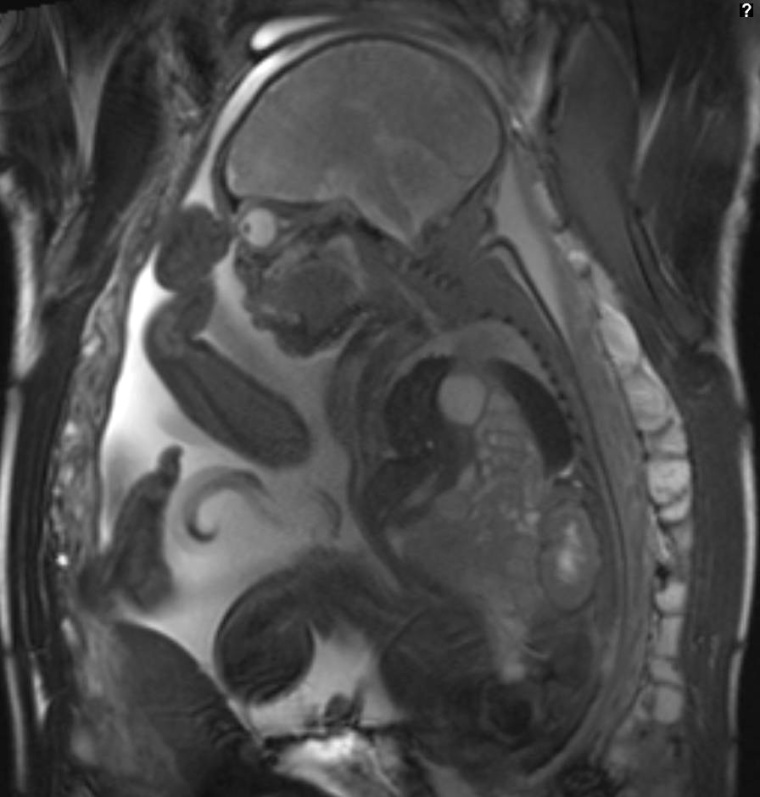

Ein relativ neues Arbeitsfeld für den Kinderradiologen ist die pränatale MRT-Diagnostik. Zunächst zwar argwöhnisch von den gynäkologischen Pränataldiagnostikern beäugt, gehört sie inzwischen in jedes ernst zu nehmende Fetalzentrum. Die Erfahrung, dass es sich beim fetalen MRT nicht um eine Konkurrenz zur Ultraschalldiagnostik handelt, sondern um deren logische und sinnvolle Erweiterung, ist im Bereich der Hirnbildgebung unumstritten. Grund dafür ist der deutliche überlegene Weichteilkontrast des MRT. Hirnfehlbildungen, insbesondere Migrationsstörungen und Hirnfaltungsverzögerungen, sind dadurch sicherer zu diagnostizieren. Das trifft aber in gleicher Weise auch für Fehlbildungen der hinteren Schädelgrube zu. Auch bei schwierigen Ultraschall-Bedingungen, wie einer extremen Adipositas der Mutter oder bei tief im Becken stehendem Kopf des Fetus, ist die fetale MRT-Diagnostik heute eine gute Alternative.

Im Thoraxbereich hat sich die Volumenbestimmung der fetalen Lunge bei Zwerchfellhernie als valide Zusatzinformation und als wichtiger Prognoseparameter gezeigt. Die Wahl eines geeigneten Entbindungszentrums mit ECMO-Möglichkeit und Thorax-Kinderchirurgie ist von diesen Untersuchungsergebnissen stark abhängig.

Zwar ist die Zahl der intrauterinen Interventionen in Deutschland nur gering, doch auch in diesen Fällen ist eine vorherige MRT-Diagnostik und eine interdisziplinäre Befundbesprechung meist unumgänglich. Die betroffenen Eltern werden oft in diese Fallkonferenzen eingeladen und fühlen sich dann mit ihren Problemen angenommen und gut betreut. Das führt zu einer zeitigen Bindung der Mütter an das betreuende Fetalzentrum. Dem Kinderradiologen kommt dabei im Fetalzentrum eine zunehmend wichtigere und zentrale Stellung zu.